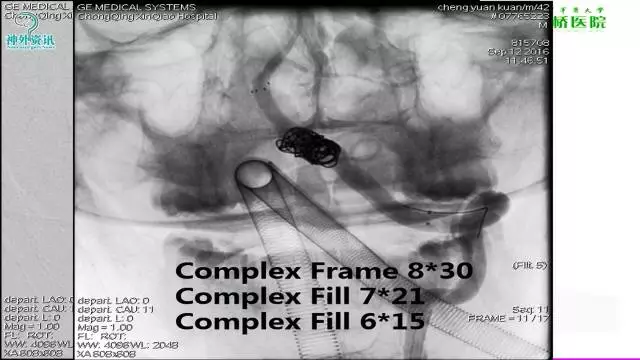

今天为大家分享的是“强生医疗CNV-神经介入专栏”第三十六期,由重庆第三军医大学附属新桥医院神经外科刘俊带来的“Galaxy弹簧圈在不规则动脉瘤中的临床应用”精彩讲课视频及PPT,欢迎观看。文章仅代表作者个人观点,如有不同见解,欢迎同道斧正!